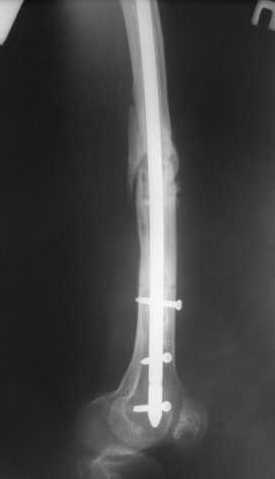

27 марта выполнено удаление блокирующих винтов (сломанный винт пришлось высверливать цапфен-бором), сломанного штифта (дистальный фрагмент удален через канал, образованный разверткой из коленного сустава - image 4),

рассверливание костно-мозгового канала, реостеосинтез штифтом UFN (при проведении штифта в дистальном отломке мы использовали поляризующий винт, диаметр штифта 10 мм). После операции в связи гемартрозом дважды (на 1 и 3 сутки) выполняли пункцию коленного сустава. Сейчас признаков скопления жидкости в полости сустава нет. Послеоперационные рентгенограммы - images 5, 6, 7.